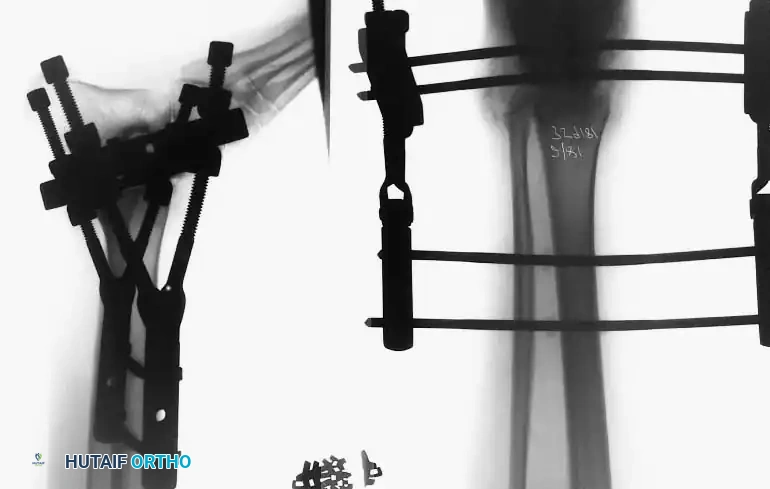

External Fixation

Historically pioneered by Charnley, external compression arthrodesis utilizes pins placed through the distal tibia and the body of the talus. Because Charnley's original uniplanar device lacked rotatory stability, Calandruccio designed a triangular frame to control motion in all three planes while applying massive compression.

Modern iterations, such as the Calandruccio II compression device, offer greater latitude in pin placement to avoid compromised skin. Ring or circular external fixators (Ilizarov, Taylor Spatial Frame) are the gold standard for salvage situations, including active infection, massive bone loss, or failed TAA, as they allow for simultaneous compression, deformity correction, and early weight-bearing.